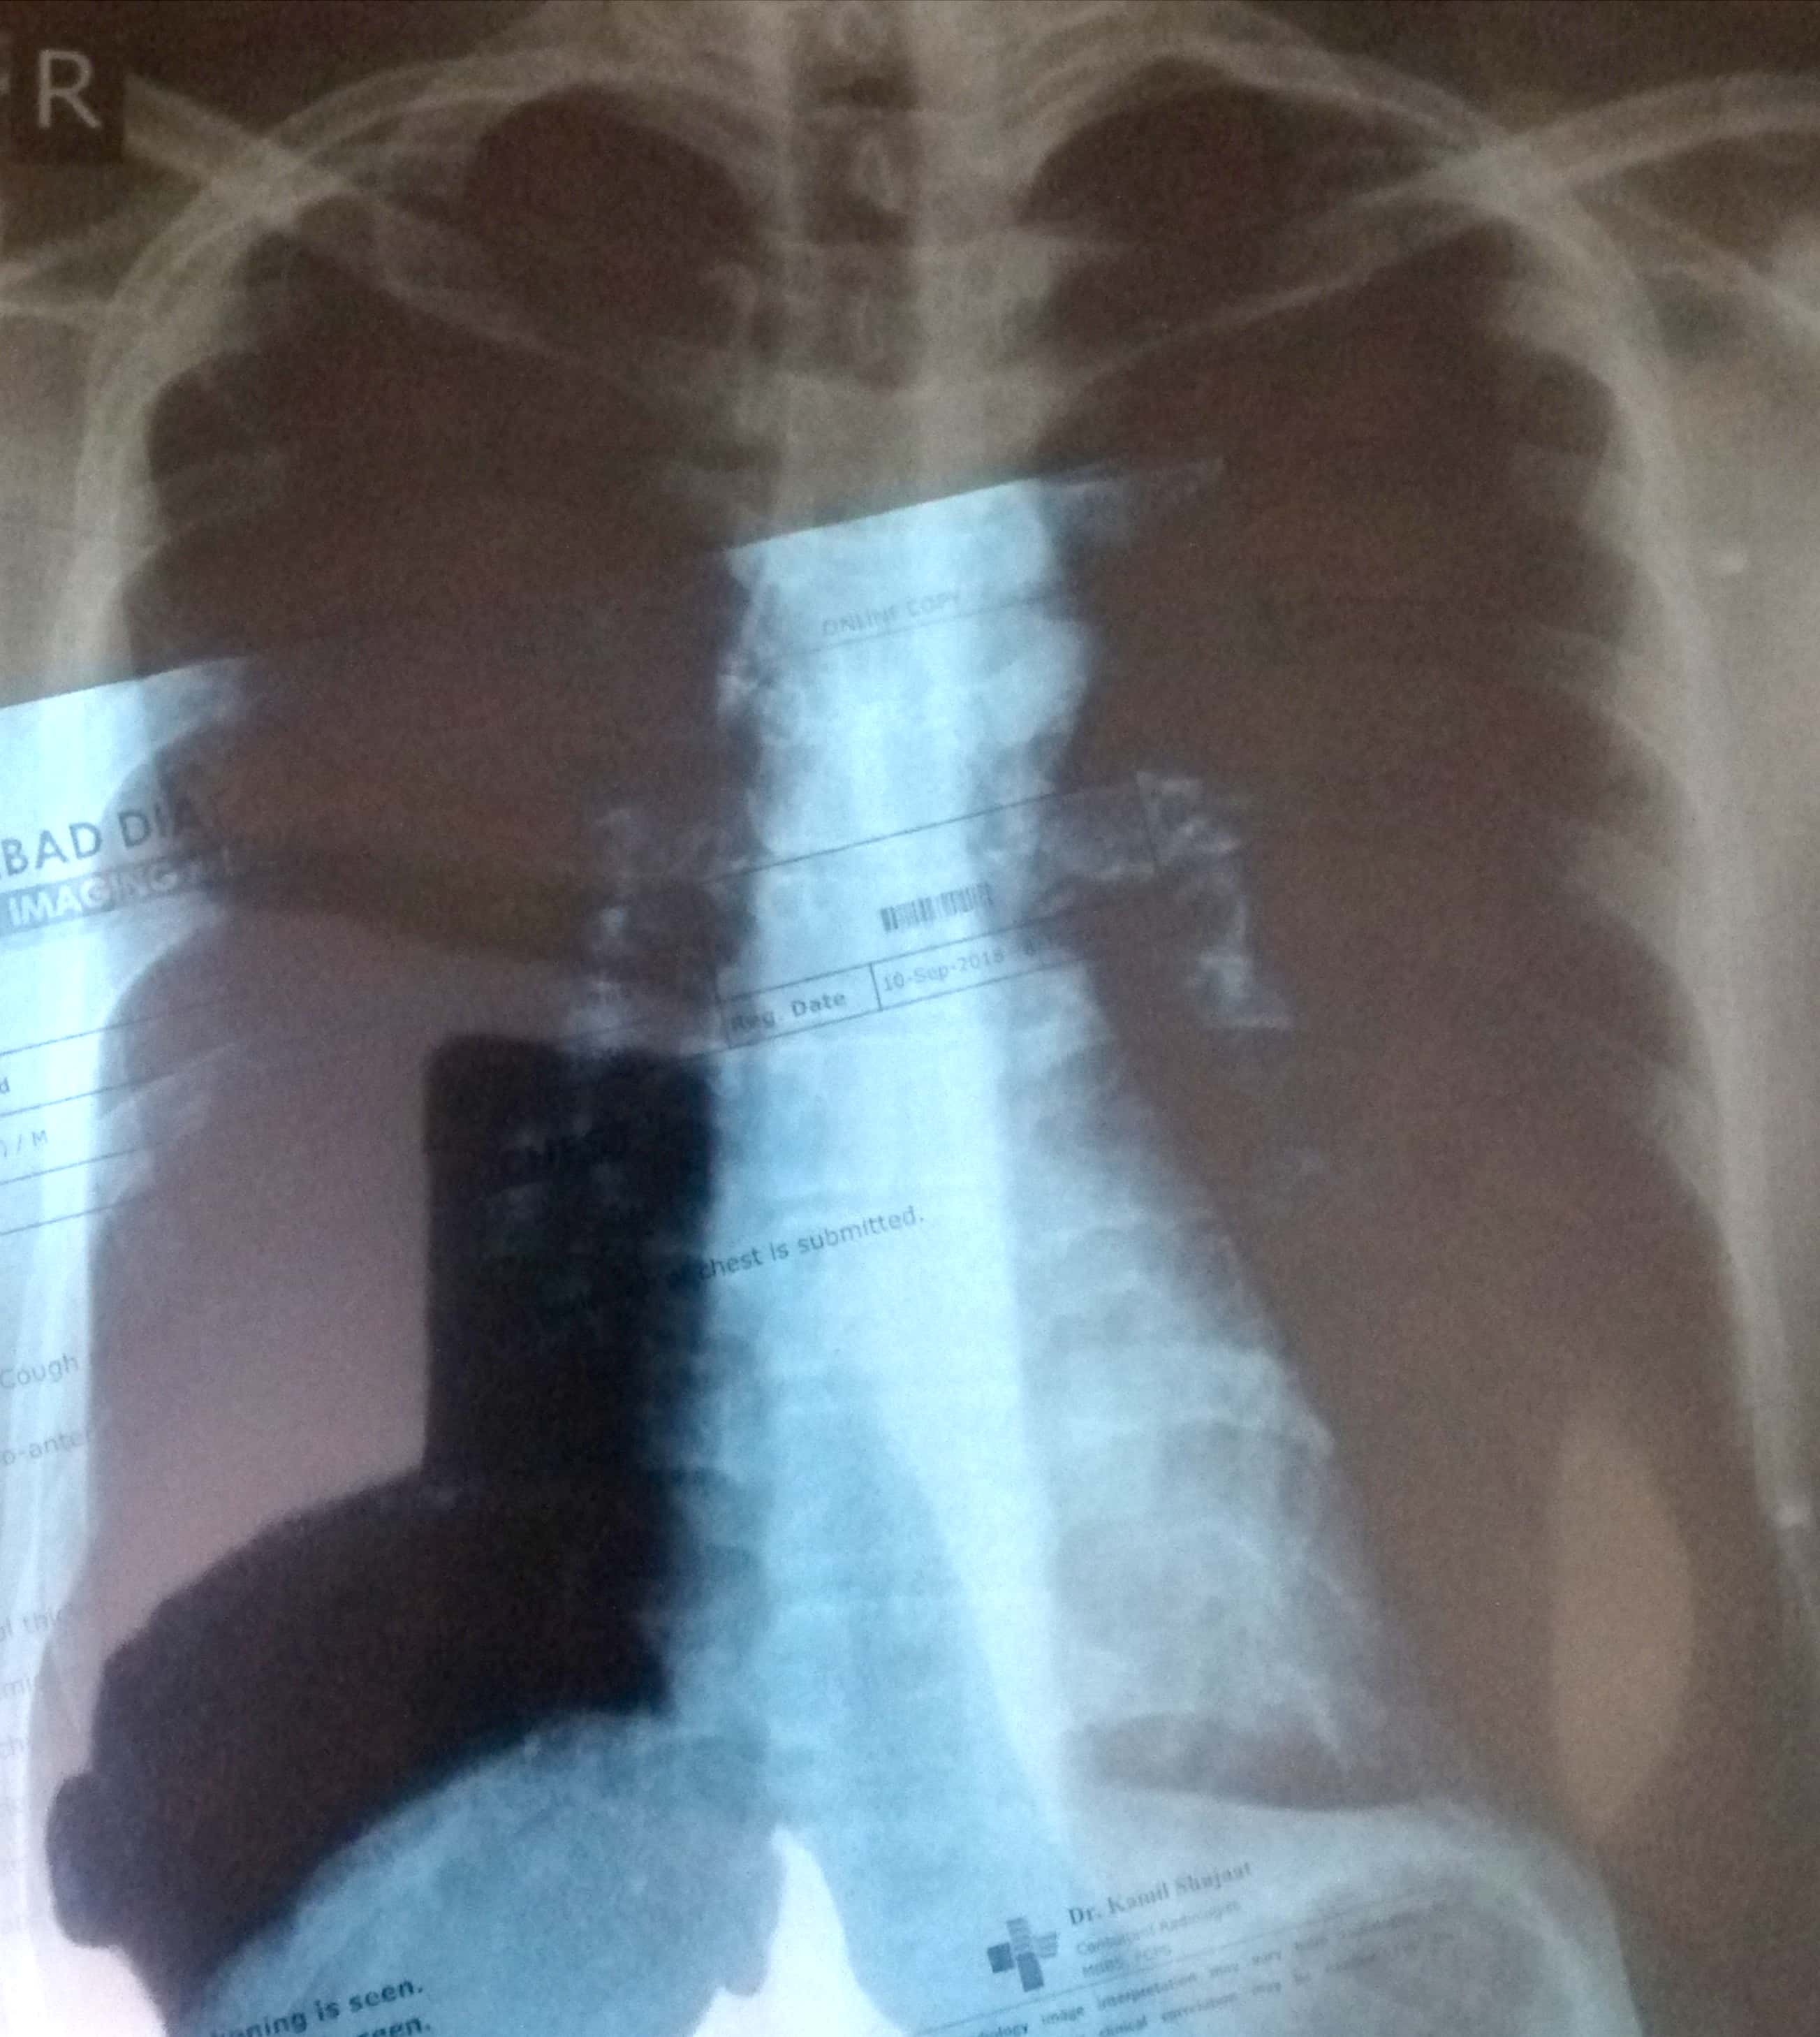

Kindly see the xray and report and guide if its normal or not

what's the complian. Xray film is not very appreciable. are you a smoker or having complain of chect infections often?

Need your history about

Fever ,cough , weight loss , anorexia and any history of chronic illness

Need complete examination and current clinic status